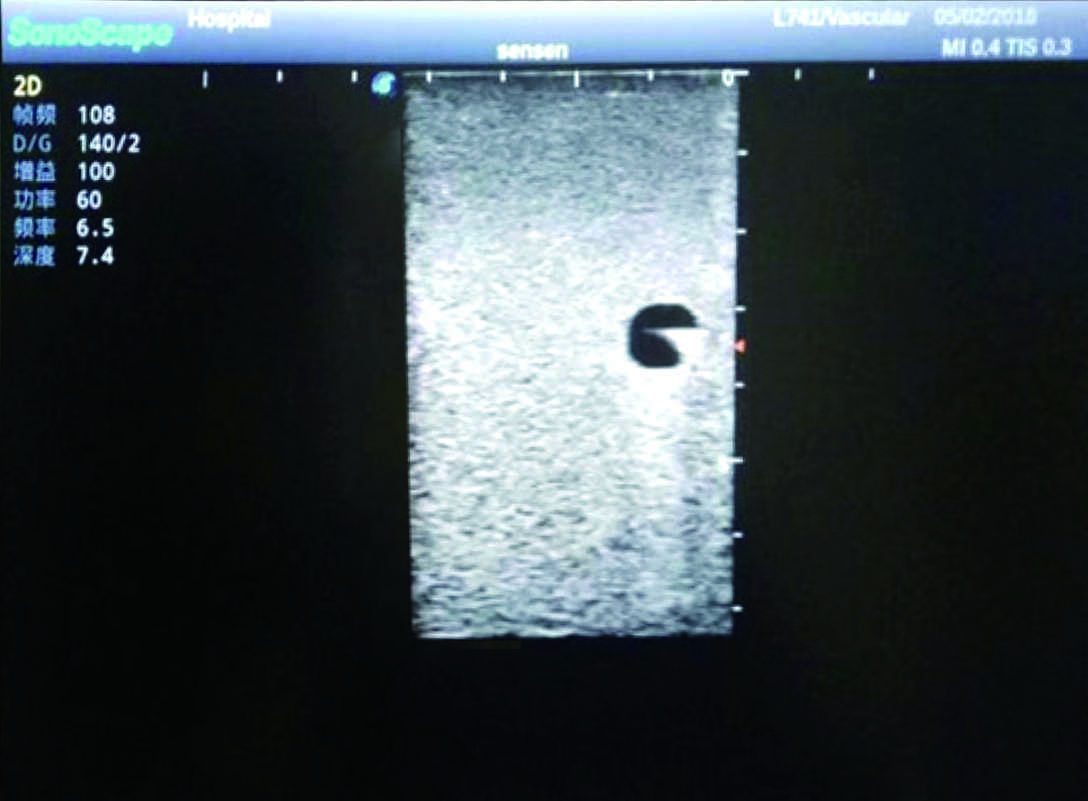

3)   Clear and real images of the tissues and organs (basilic vein and superior vena cava)

4)   When conducting vascular puncture, the piercing can be truly felt, and venous blood outflow can be seen